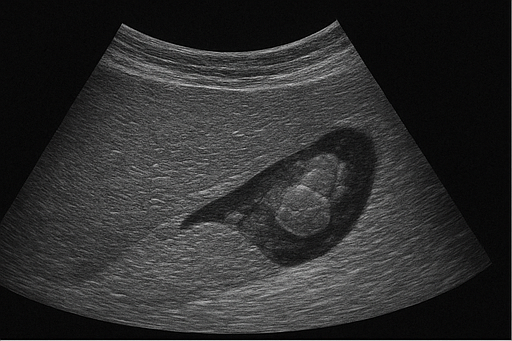

- 담석: 담낭이나 담관에 생긴 돌로, 초음파에서 밝은 음영과 그림자로 나타납니다.